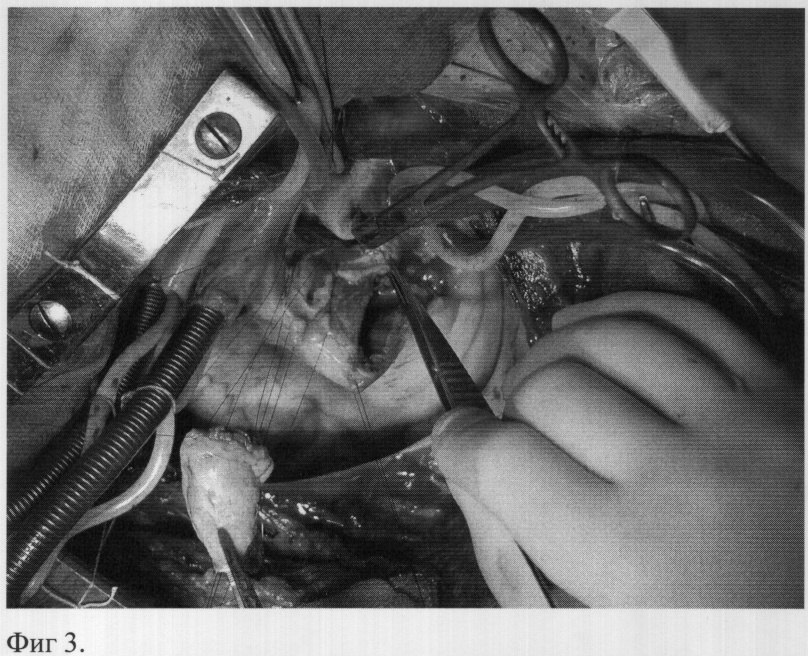

Имплантируют в аортальную позицию легочный аутографт, ориентируя его таким образом, чтобы существовало анатомическое соответствие устьев коронарных артерий синусам Морганьи, а также и соответствие мышечного продолжения аутографта дефекту основания аорты. Сначала проводят три П-образных шва (пролен 4/0) через комиссуры аутографта и через окружающие ткани в области локализовавшихся ранее комиссур корня аорты (фиг.3), аутографт выворачивают в левый желудочек и прошивают по основанию к тканям корня аорты обвивным швом от комиссуры до комиссуры, закрывая при этом дефекты корня аорты (фиг.4). Затем поочередно реимплантрируют устья коронарных артерий, левое, затем правое (пролен 5/0), формируют дистальный анастомоз между легочным аутографтом и восходящим отделом аорты. В позицию легочного ствола имплантируют биологический кондуит обвивными швами (дистальный анастомоз пролен 4/0, проксимальный пролен 3/0).